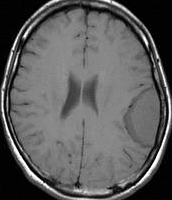

手術後のMRIです。腫瘍は全部取れていて後遺症もありません。圧迫されて変形していた脳はきれいに元に戻っていますし脳浮腫も消えました。一般的に若い人の脳ほどきれいに元に戻ります。注意しなければならないのは,少しでも取り残した場合には,何年か後に10%-20%くらいで再発があることです。もちろん完全に取れた時の再発はほとんどありません。